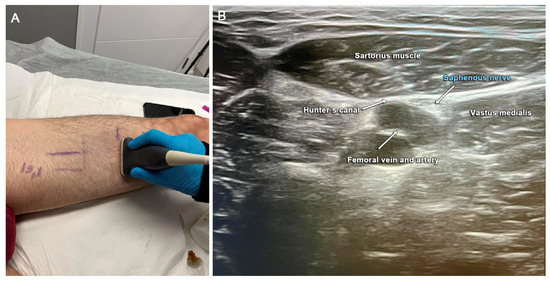

2.2. Diagnostics

2.3. Surgical Technique